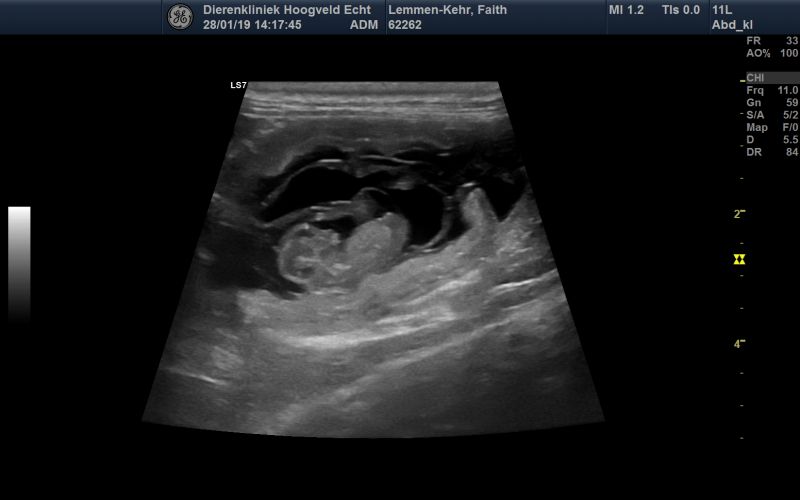

28.01.19

Trächtigkeitstag: 30

Bauchumfang: 53 cm

Gewicht: 15,5 Kilo

Heute waren wir zum Ultraschall. Vier kleine Welpen konnten gefunden werden. Anfang März wird es also soweit sein. Die Zitzen von Faith sind schon angeschwollen und gut durchblutet. Sie ist deutlich ruhiger geworden und schläft recht viel. Ab heute bekommt sie Dorschlebertran und Canosan ins Futter. Zudem erhöhen wir den Vitamin und Proteingehalt. An der Menge ändert sich noch nichts.

Bin mächtig glücklich gerade.